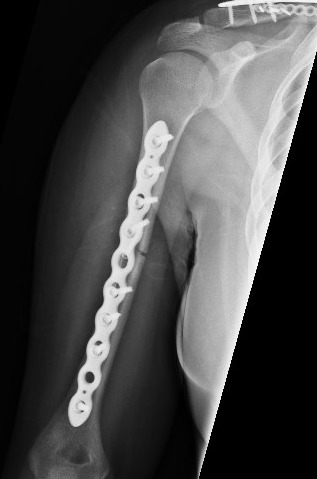

Open Reduction and Internal Fixation (ORIF) is the most common method of providing operative stabilization of humeral shaft fractures.1 The treatment choice can be performed through numerous approaches addressing various injury characteristics (i.e., fracture pattern, soft tissue injury, radial nerve damage, etc.) Recent biomechanical studies have shown the added strength of a second plate applied to the shaft.2–4 A single plate is typically used for ORIF of humeral shaft fractures [Figure 1].

The second plate, whether orthogonal or in parallel, increases stability and reduces the risk of hardware failure prior to healing [Figure 2, Figure 3].5 Although there is evidence for the benefits of ORIF, there is limited data on how plate number and size may affect outcomes such as union rate, pain scale, and other complications.6–8 There may be added implant costs to adding a second plate to a humeral shaft fracture, but we know of no specific contraindications. This study compares the radiological and surgical outcomes of single and dual-plating techniques. Our primary null hypothesis was that there is no statistically significant difference in the union rate between single versus dual plating for humerus shaft fractures. Our secondary hypothesis is that there is no significant difference in the rate of complications and pain level between single and dual plating.